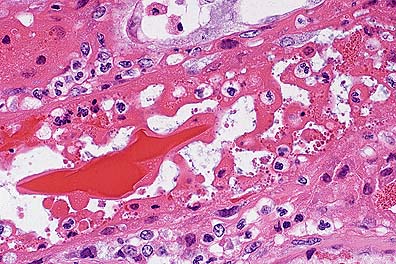

Interstitial hemorrhage and proteinaceous casts within the renal tubules of an 11-year-old Quarterhorse. (HE, 100X, 56K).

Tubular epithelial necrosis and cellular casts in the kidney of a horse with red maple intoxication. (HE, 400X, 52K)

Proximal tubular epithelial necrosis and hemoglobin cast formation in the proximal renal tubules of a horse with red maple intoxication. (HE, 400X, 59K)

Contributor's Diagnosis and Comments: Hemoglobinuric nephrosis, equine due to red maple leaf poisoning.

AFIP Diagnosis: Kidney: Necrosis, tubular, acute, multifocal, moderate, with granular, intratubular, brightly eosinophilic material, and hemoglobin crystals, Quarterhorse, equine.